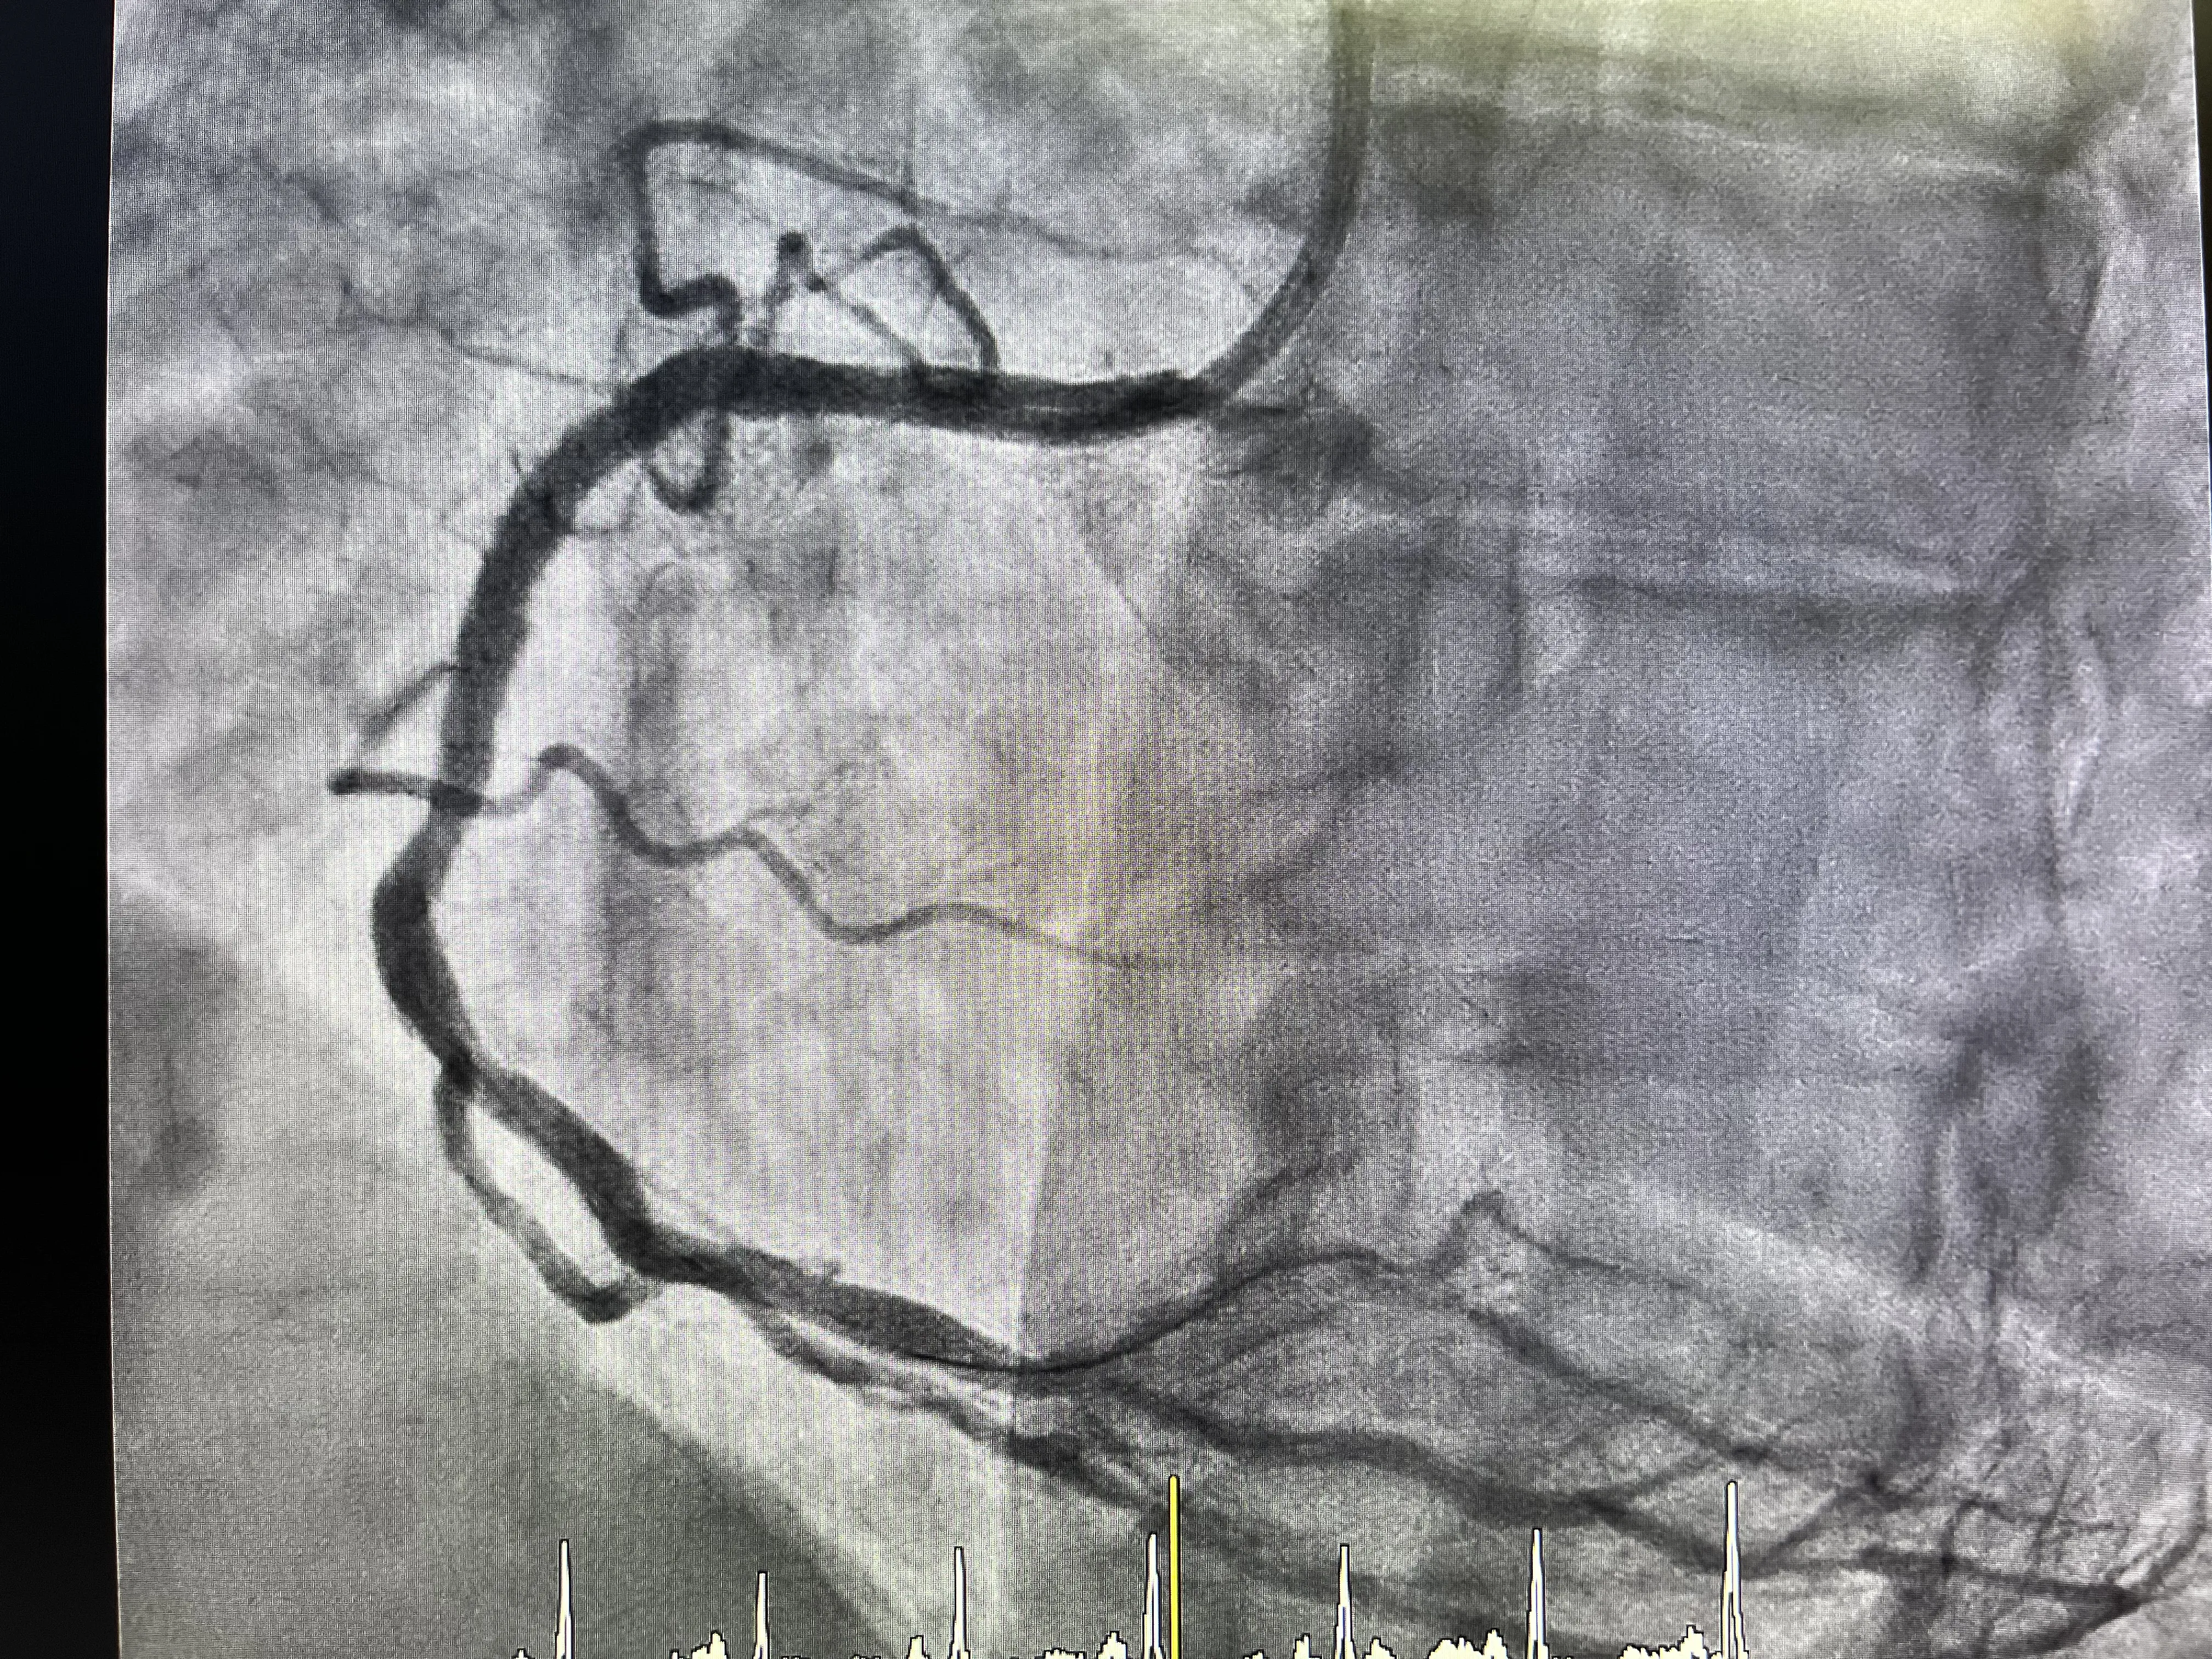

El primer paso técnico en este caso real fue realizar un cateterismo diagnóstico del árbol coronario izquierdo. Para ello se utilizó un catéter diagnóstico estándar, cuyo objetivo principal es visualizar de forma detallada la anatomía de la coronaria izquierda y sus ramas principales. Esta fase permite descartar lesiones críticas en el territorio izquierdo que pudieran requerir tratamiento inmediato o modificar la estrategia global. Aunque el infarto fuera inferior, no se puede asumir que el resto del árbol coronario esté libre de enfermedad significativa.

La angiografía del árbol coronario izquierdo se llevó a cabo de manera sistemática, obteniendo proyecciones que permitieran una valoración completa. El hecho de que el foco del infarto fuera inferior no exime de revisar con atención la descendente anterior y la circunfleja. En este caso, la exploración del lado izquierdo se realiza sin incidencias reseñables, lo que refuerza la sospecha de que la arteria responsable del evento agudo es la coronaria derecha. Una vez completada esta parte diagnóstica, se pasa a la fase terapéutica centrada en el vaso culpable.